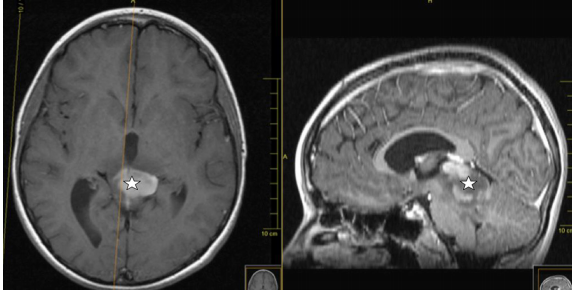

原发性颅内间变性神经节胶质瘤是一种少见的儿童肿瘤。他们大多表现为血压升高或癫痫症状。轴外定位比轴向定位更常见。核磁共振检查中类似毛细胞性...